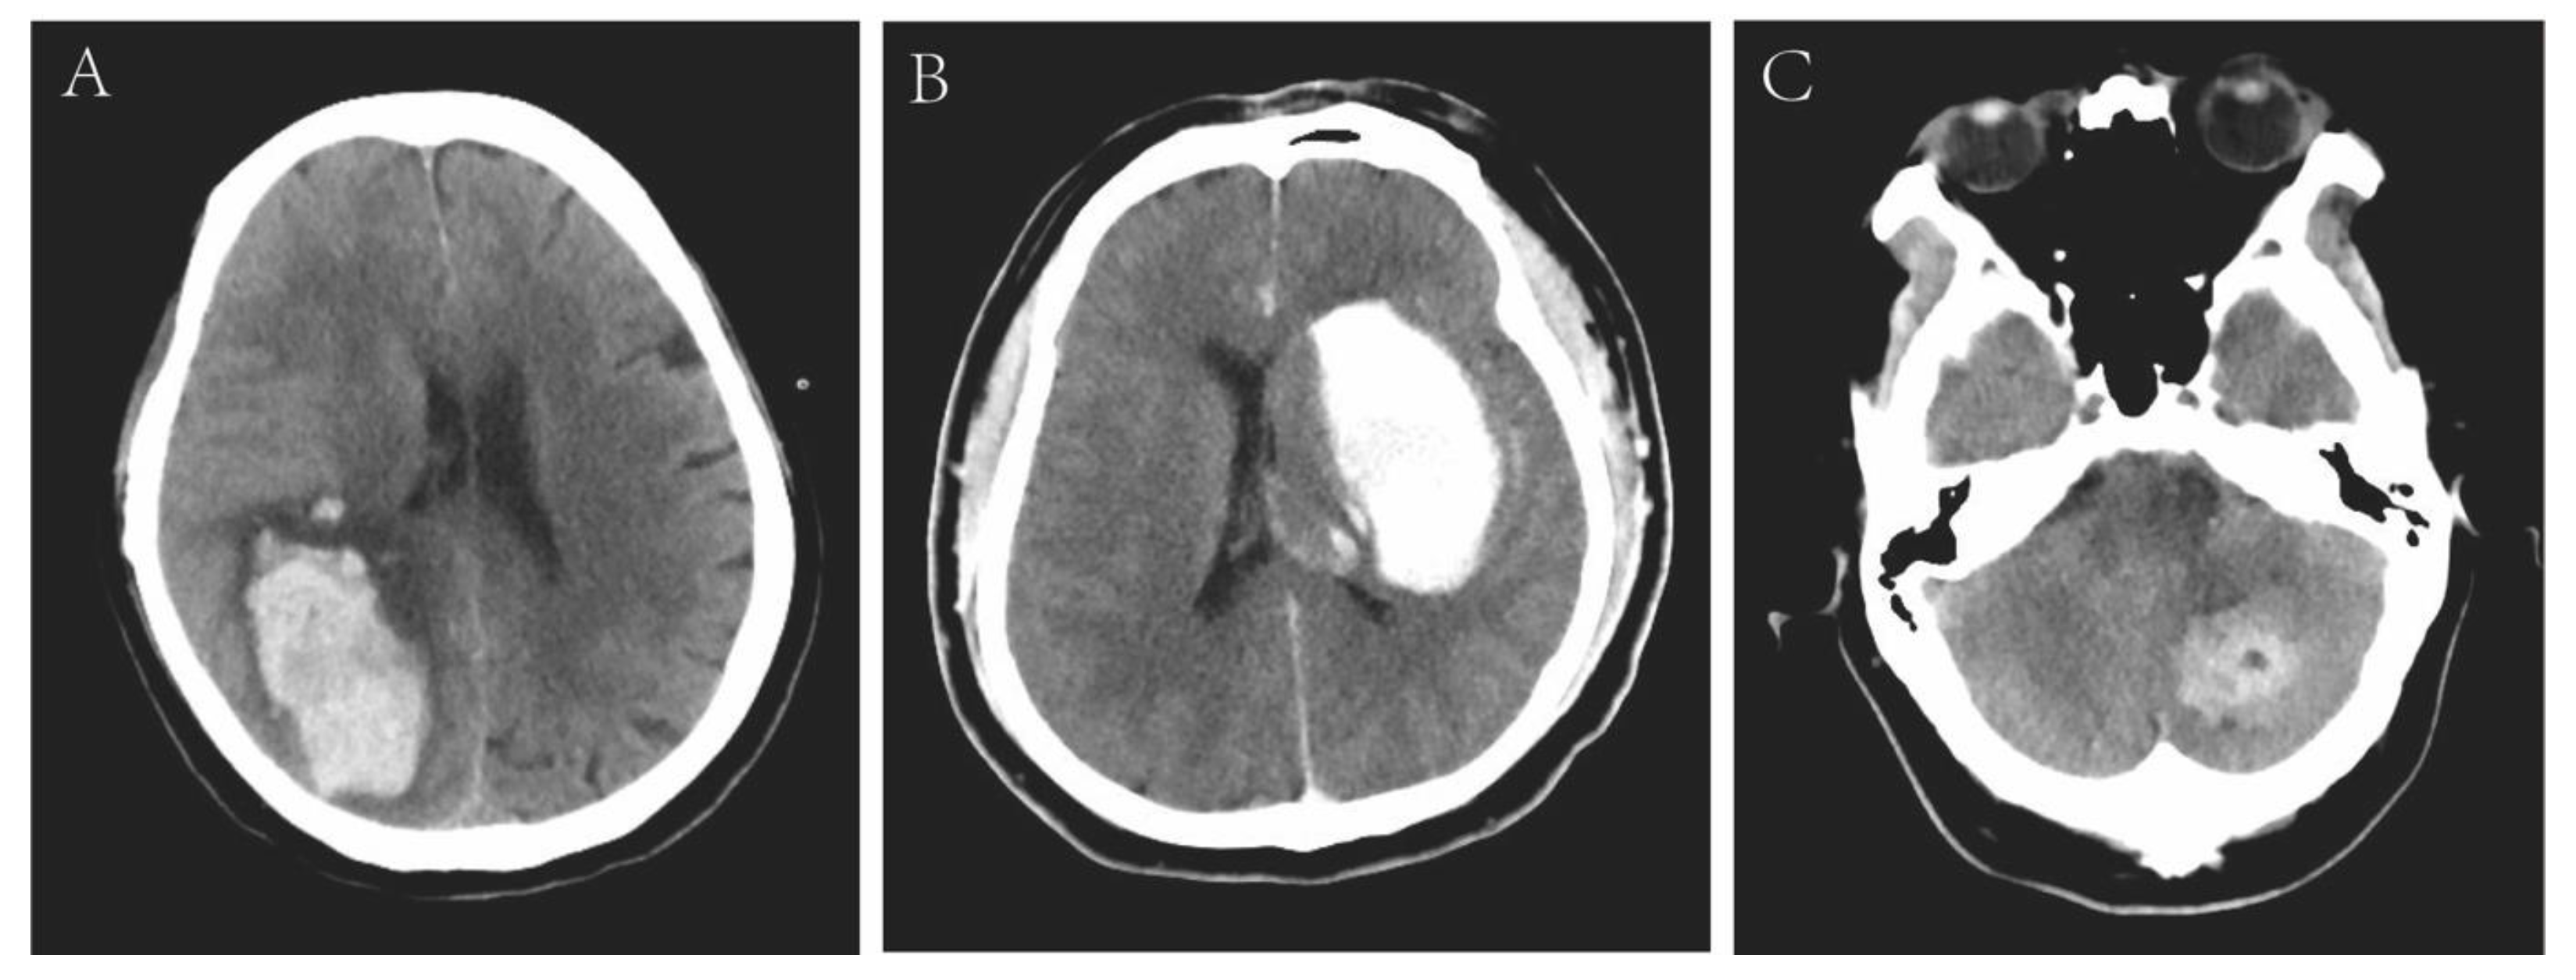

| Neuroradiologic data | ||||

| Location 1 | 0.109 | |||

| Lobar | 12 (66.7) | 10 (76.9) | 2 (40.0) | |

| Cerebellar | 4 (22.2) | 1 (7.7) | 3 (60.0) | |

| Deep (basal ganglia and thalamus) | 2 (11.1) | 2 (15.4) | 0 (0) | |

| Location 2 | 0.044 | |||

| Infratentorial | 4 (22.2) | 1 (7.7) | 3 (60.0) | |

| Supratentorial | 14 (77.8) | 12 (92.3) | 2 (40.0) | |

| Combined with SAH | 4 (22.2) | 4 (30.8) | 0 (0) | 0.278 |

| ICH volume, cm3 | 65.83 ± 53.34 | 84.17 ± 50.74 | 18.14 ± 20.85 | 0.001 |

| Small (<30 cm3) | 5 (27.8) | 1 (7.7) | 4 (80.0) | 0.008 |

| Large (≥30 cm3) | 13 (72.2) | 12 (92.3) | 1 (20.0) | 0.008 |

| Brain herniation | 4 (22.2) | 4 (30.8) | 0 (0) | 0.278 |

| Intraventricular hemorrhage | 2 (11.1) | 2 (15.4) | 0 (0) | 1 |

| Midline shift ≥ 10 mm | 6 (33.3) | 6 (46.2) | 0 (0) | 0.114 |